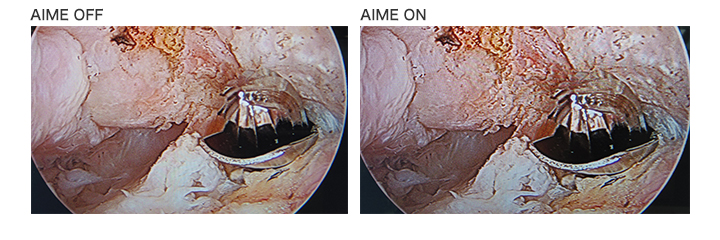

A.I.M.E.画像処理への印象は?

私が関節鏡で実施している肘の分野は、肩や膝とは違い、神経の位置の関係で、”スコープを操作するポータル(Viewing portal)”と”器械を操作するポータル(Working portal)”が2か所と少なく、関節鏡からの視野が限られています。

A.I.M.E.機能は、奥行き感や色の再現が優れており、私が知り得たい部位・箇所について、実際に開いて触ってみないと判断できないようなケースでも、画面上で容易に見当がつけられると感じました。肘の症例では、該当組織の切除等の判断時は、限られた関節鏡から得られる情報が非常に重要となります。写真では分かりづらいですが、実際の映像では、境界部分の判断や処置の過程の認識がしやすくなりました。

A.I.M.E.機能では、従来のモニターよりも、立体感や質感などや、色彩の再現が素晴らしく、術者への負担低減の貢献が期待できます。

A.I.M.E.™ (Advanced Image Multiple Enhancer)は、内視鏡カメラなどからの医療画像を内蔵画像処理技術(ハードウェア処理)により、高速に、コントラストや色を強調できるソニーの独自の技術です。従来のエッジをシャープにする強調とは異なり、構造物自体を強調します。

ユーザーは好みに応じて、色強調機能は8段階から、ストラクチャー強調機能は4段階から選択ができ、また、同時にこれらを組み合わせて使用することも可能です。